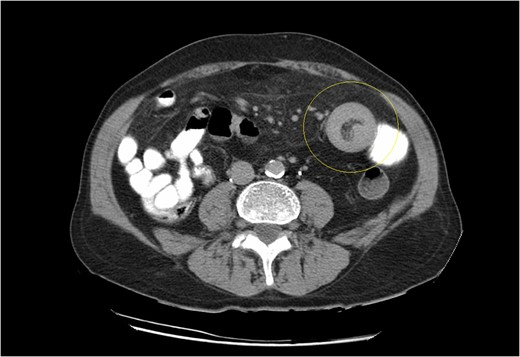

(a, b) Small bowel intussusception located in the proximal jejunum.

Computed tomography is the modality of choice for diagnosis of an intussuscepted bowel loop, with a sensitivity and specificity of ~80% and 100%, respectively. Depending on sagittal or axial view, findings may include the presence of concentric rings due to duplication of small bowel layers (‘doughnut’ or ‘target’ sign), or a sausage shaped mass [3, 5, 6]. U/S scan is also useful for identification of intussuscepted bowel with the typical ‘target sign’ [6]. Diagnosis is usually set intraoperatively, because of the nonspecific clinical symptoms and non-pathognomonic radiological findings.